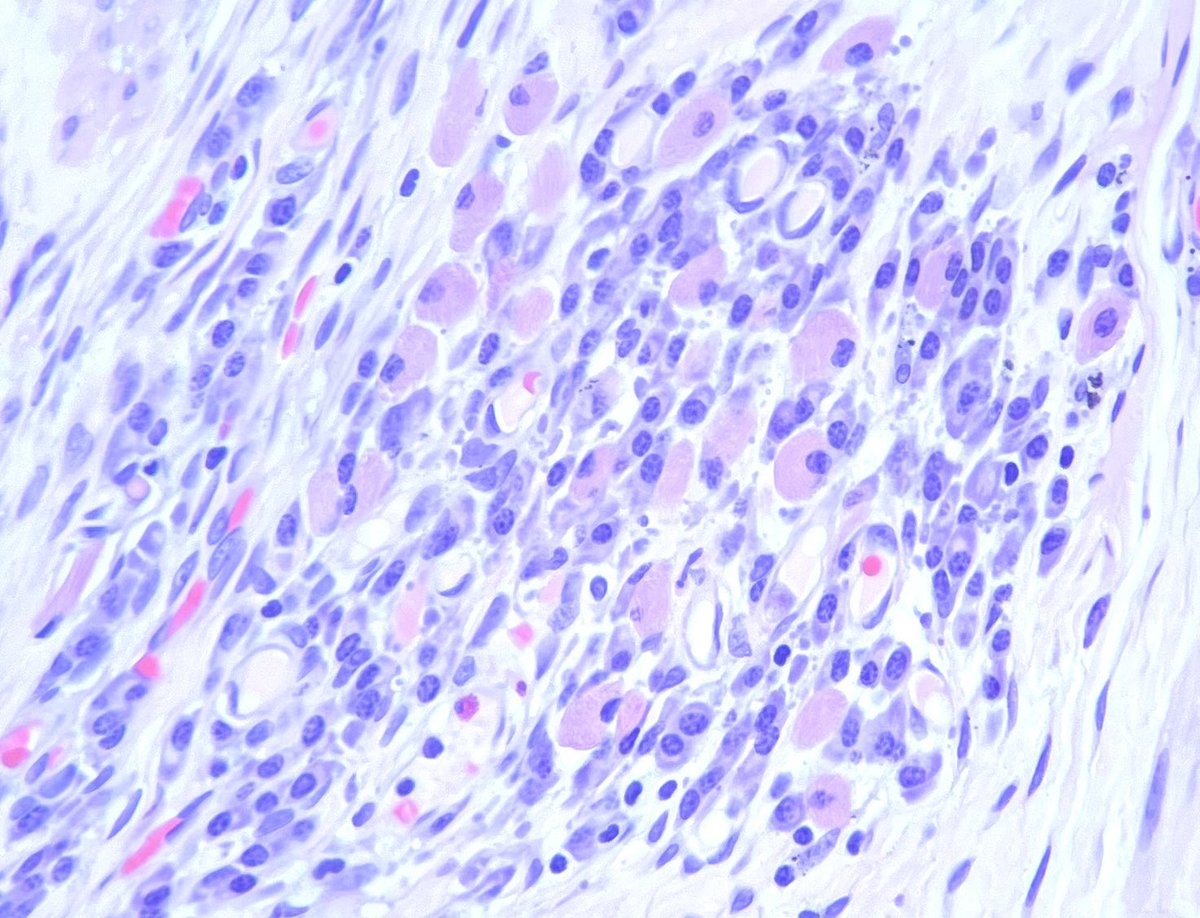

This is a group of plasma cells. Some of them contain Russell bodies, which are cytoplasmic inclusions containing immunoglobulins. We often associate these with Russell body gastritis, but this is in an ileostomy in a patient with Crohn’s #gipath Zucker Pathology Residency